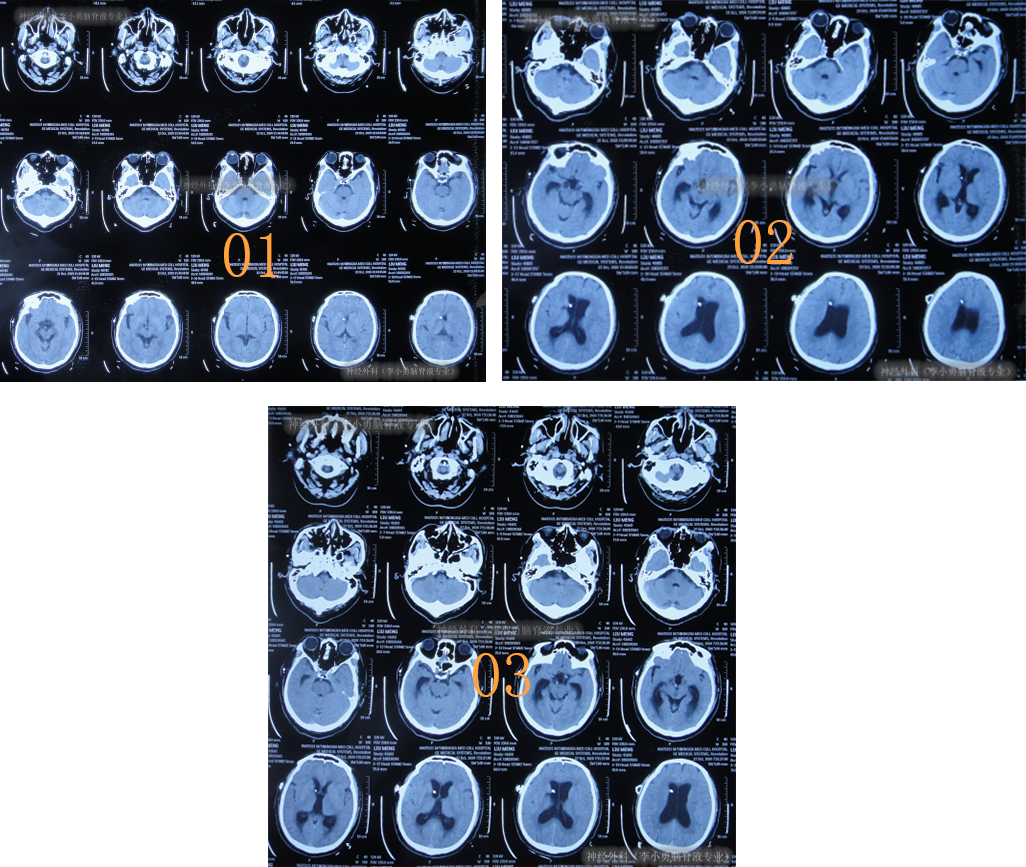

住院1周左右时间,期间曾3次查头颅CT(图-2)示脑室稍有扩张,但头晕症状慢慢消失,行走不稳缓解,认为“病情变好”出院。

图-2:3次查头颅CT

但出院后1个月即2020年12月6日(脑室腹腔分流术后3年零2月),再次出现嗜睡,第3次就诊该院,查头颅CT(片子丢失)后认为脑室系统与1月前相比并未明显扩张,但第2天即2020年12月7日,出现昏迷,大小便失禁,再查头颅CT(图-3)后认为脑室有大。

图-3:2020年12月7日头颅CT